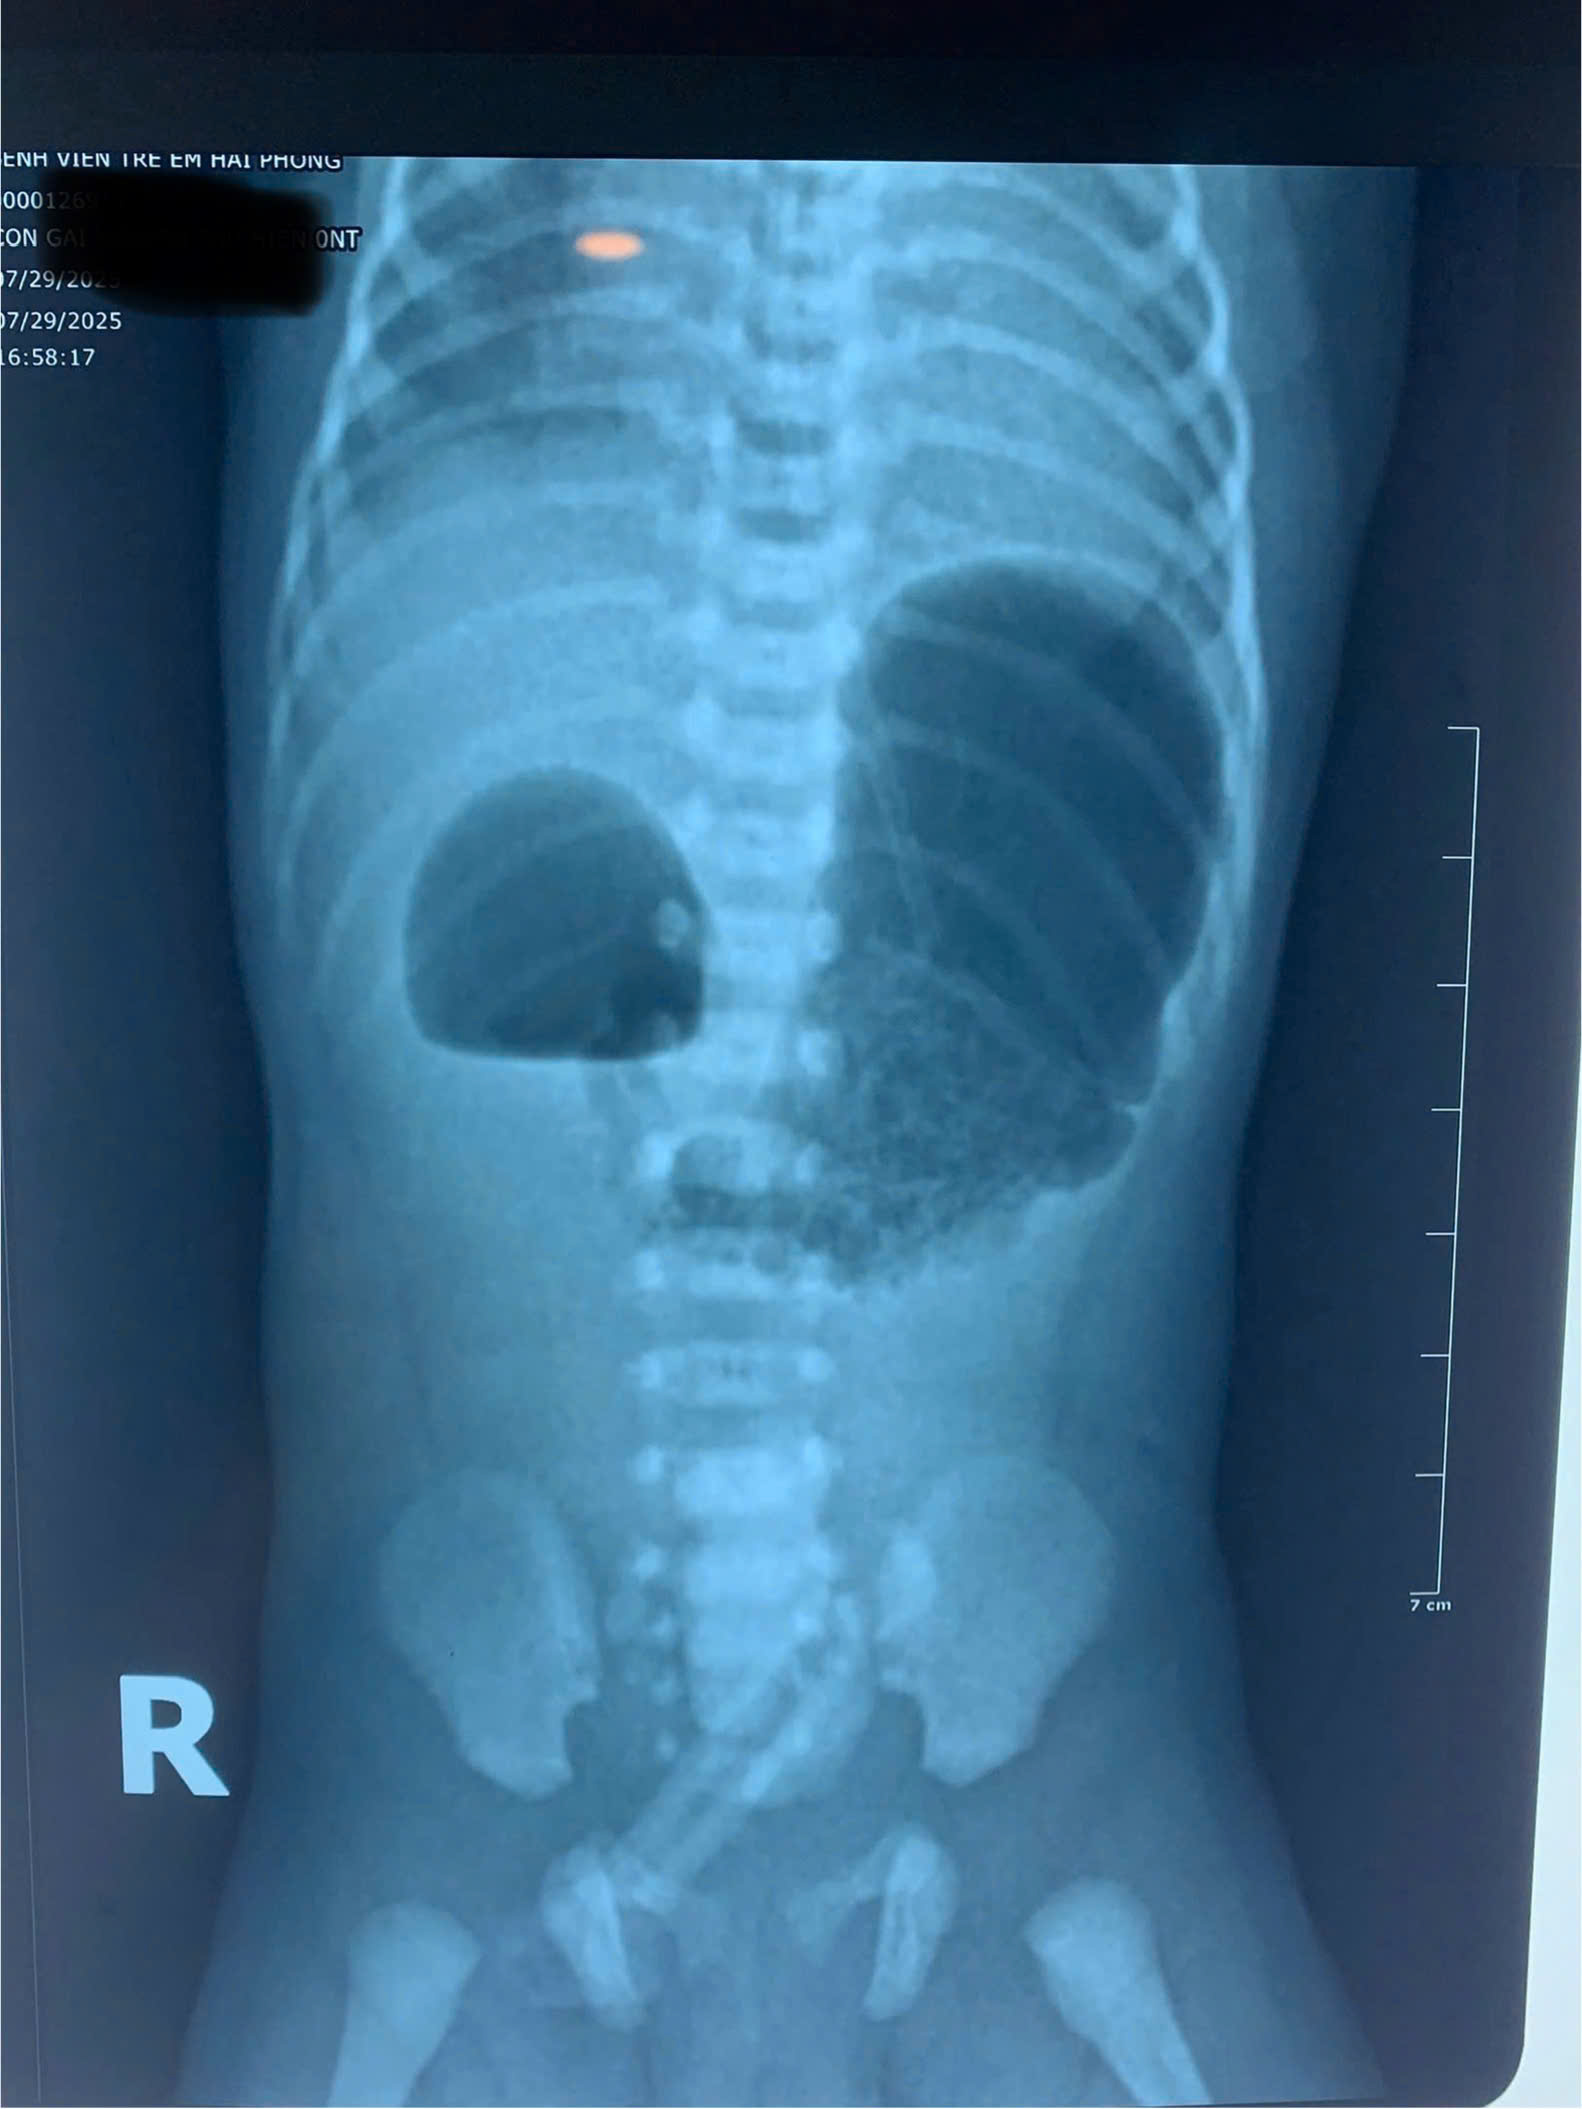

Khi nhập viện, bé ở trong tình trạng mất nước, thóp lõm, rối loạn điện giải và thiếu máu. Các bác sĩ đã nhanh chóng tiến hành hồi sức tích cực, nuôi dưỡng tĩnh mạch và bù điện giải, quá trình khám và làm các xét nghiệm chẩn đoán hình ảnh phát hiện trẻ bị tắc tá tràng bẩm sinh. Sau điều trị hồi sức, sức khỏe bé tạm ổn định các bác sĩ nhanh chóng tiến hành phẫu thuật để lập lại lưu thông đường tiêu hóa bằng phương pháp nối tá – tá tràng.

Đây là căn bệnh hiếm gặp với tỷ lệ mắc từ 1/5.000 đến 1/10.000 trẻ. Bệnh có thể được phát hiện sớm qua siêu âm từ tuần thai 18-20 với dấu hiệu như mẹ đa ối và hình ảnh dạ dày tá tràng phình lớn do tắc nghẽn, sau sinh trẻ thường có nôn trớ ra dịch xanh, vàng. Trẻ cần được chẩn đoán sớm sẽ giúp điều trị kịp thời sau sinh, ngăn ngừa các biến chứng nguy hiểm.